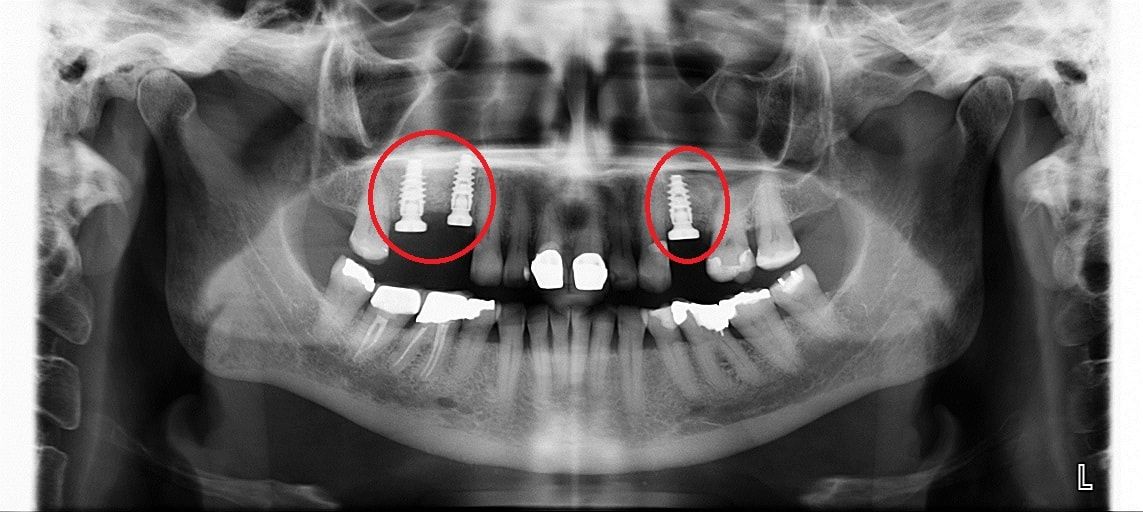

• до синус-лифтинга

• после синус-лифтинга

• после установки имплантатов в верхнюю челюсть

• коронки установленные на имплантаты